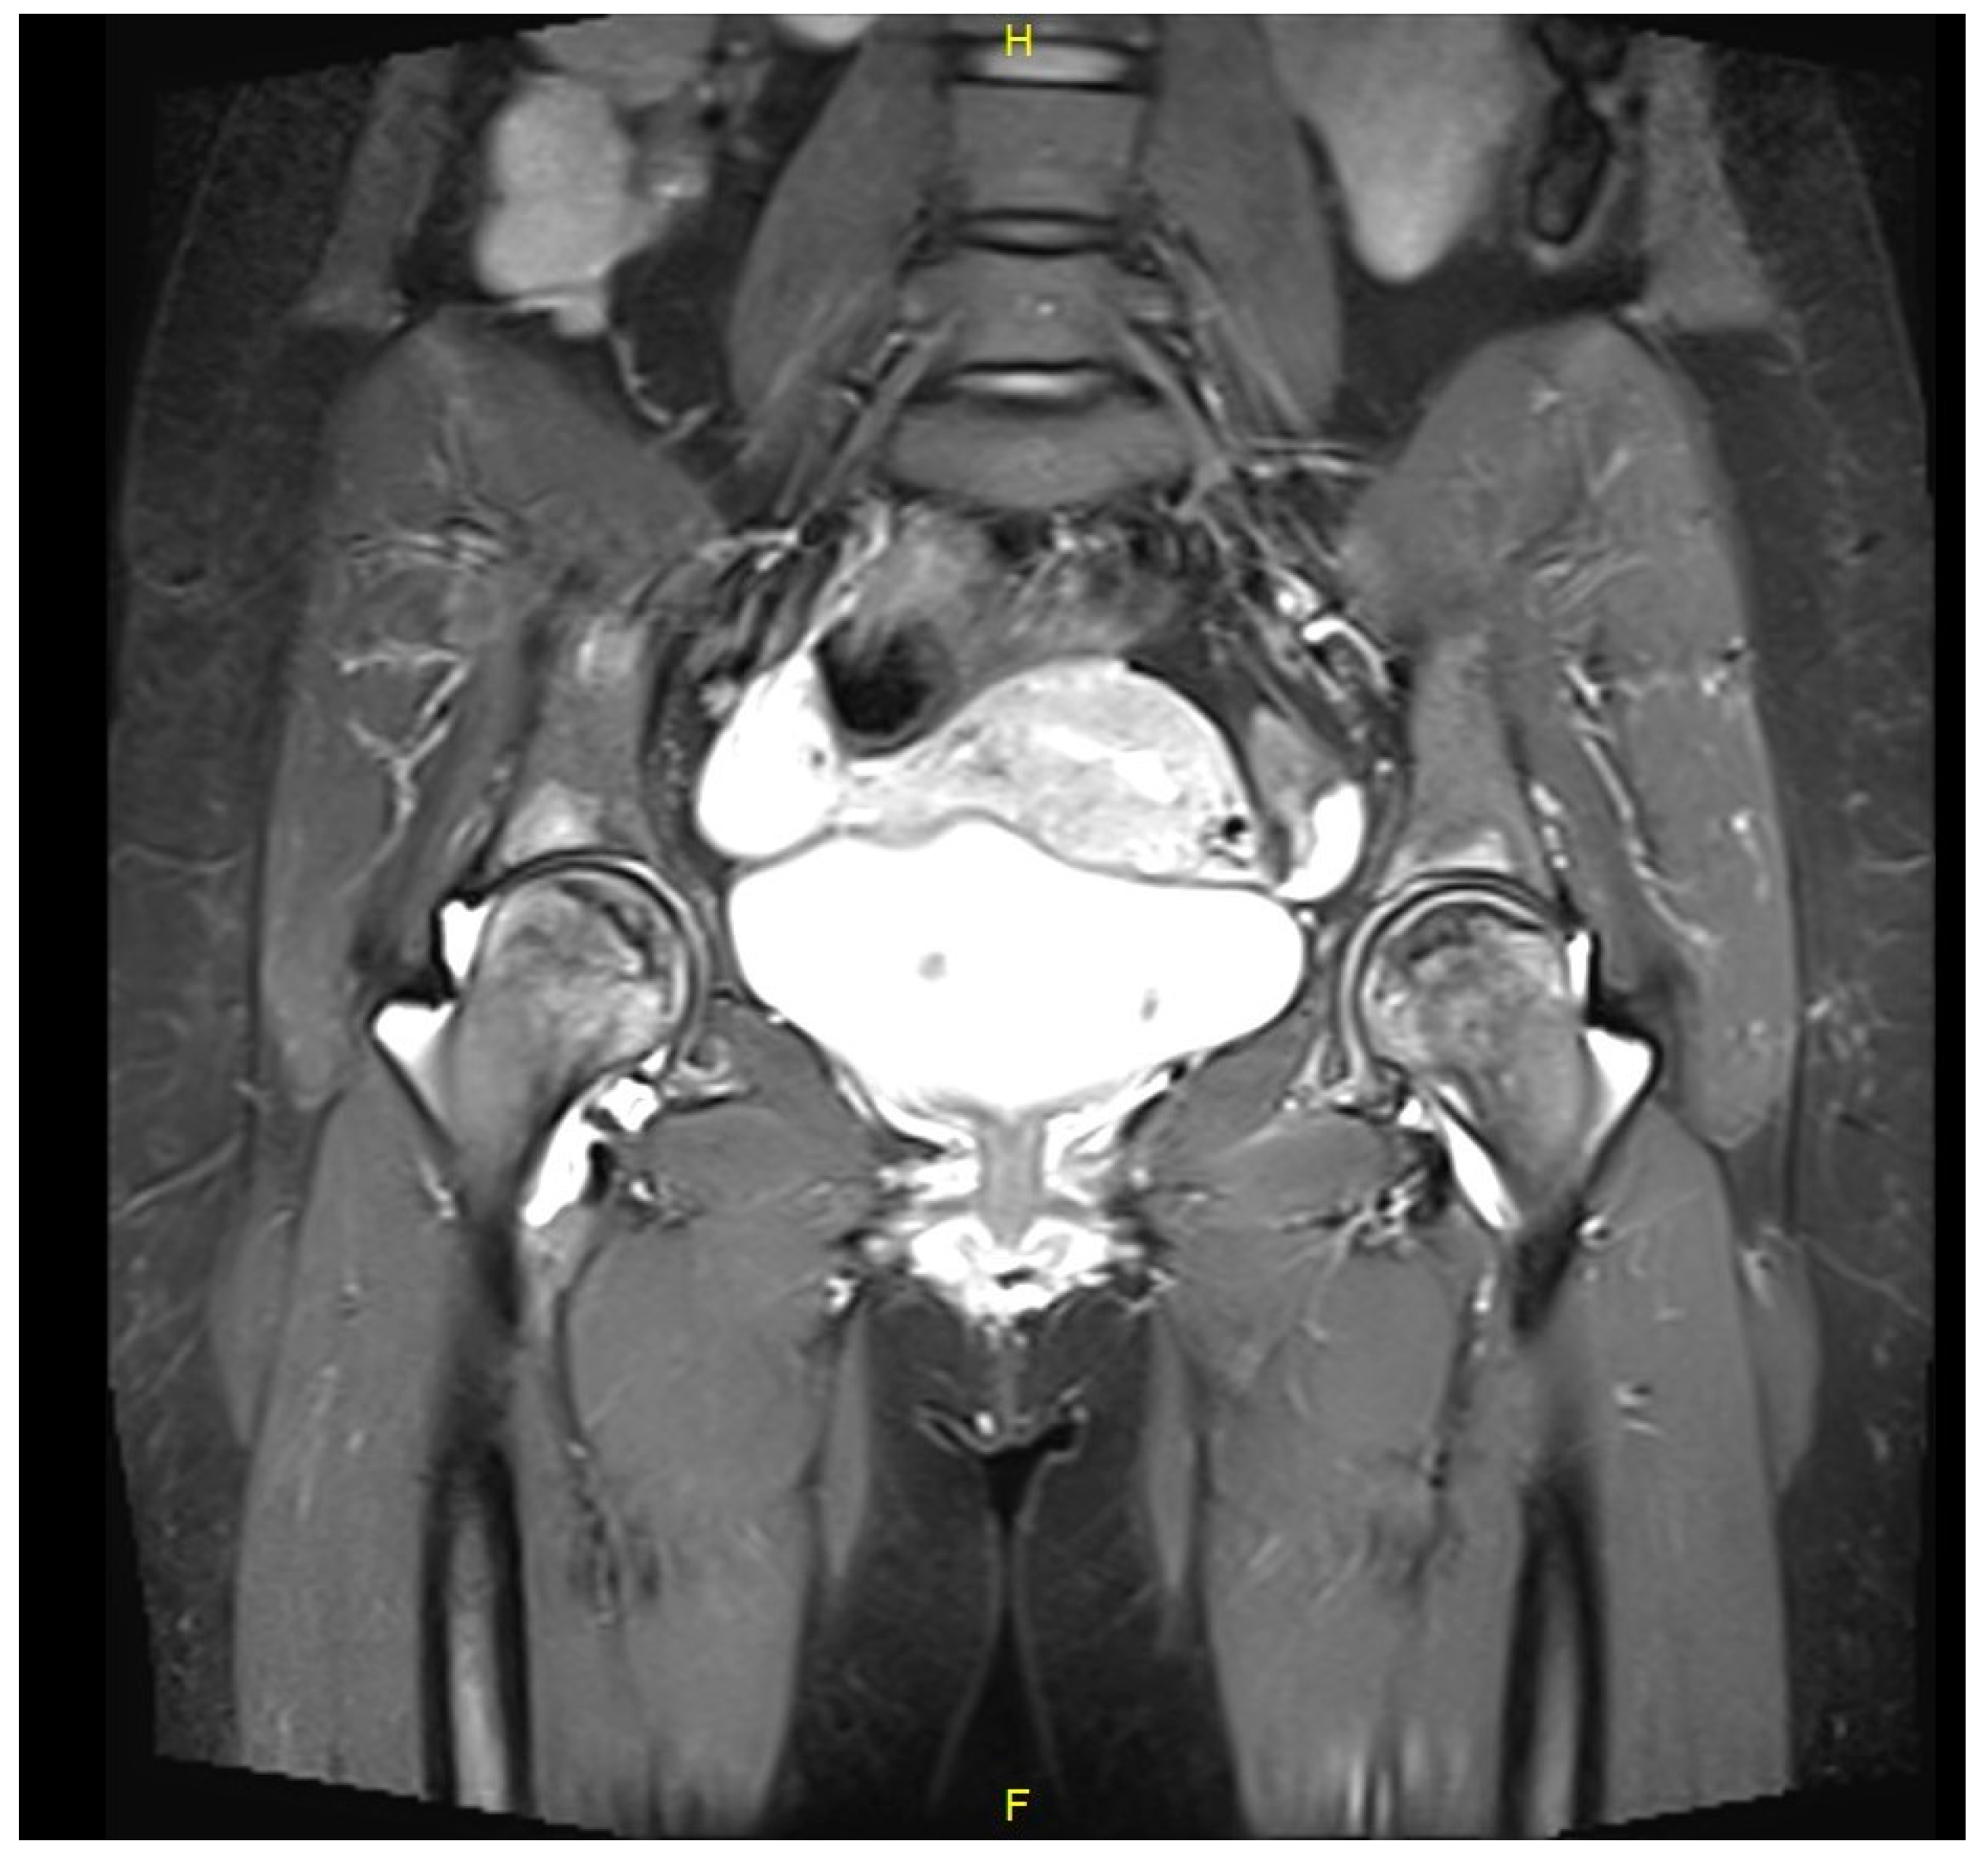

Figure 1.

A coronal plane t-2 weighted MRI of pelvis and hip joints of Case 1 showing bilateral pre-collapse changes of femoral heads and joint effusions. These findings are compatible with simultaneous bilateral osteonecrosis.